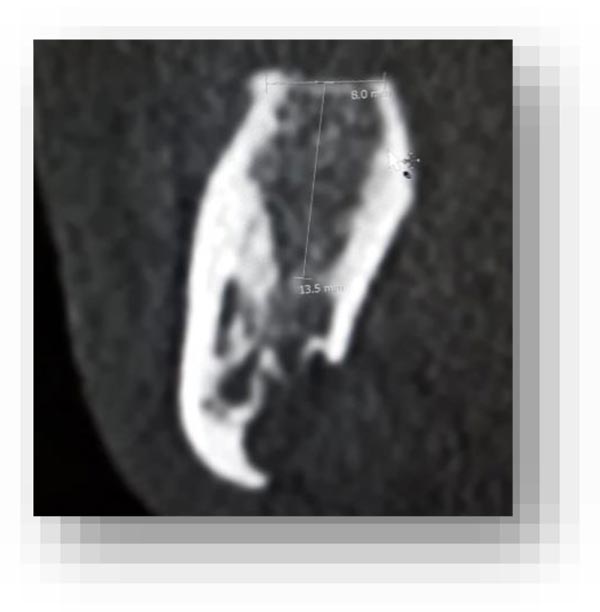

In this radiographic exam, we found an oval notch with radiolucent, clear and regular borders, located in the inferior portion of the horizontal branch of the mandible, on the lingual side, near the angle of the mandible, and below the mandibular canal. The X-ray allowed precise measurement showing a height ranging between 13.5 mm and 17 mm and breadth between 6 and 8 mm (Figs. 4-5).